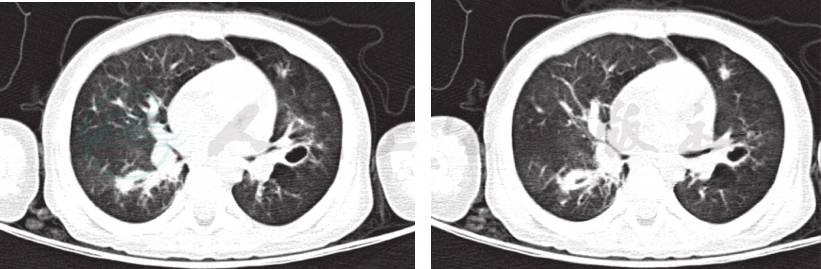

入院后完善各项检查:血常规、CRP等感染指标均正常;肺炎支原体抗体-IgM、IgG抗体均阴性;肺炎衣原体抗体阴性;结核抗体(TBAb)、常见呼吸道、肠道病毒及肝炎病毒检测均阴性,血细菌培养未见细菌生长,结核菌素试验阴性,G试验、GM试验阴性;免疫球蛋白及T淋巴细胞亚群无特殊异常。入院后予抗感染、布地奈德联合复方异丙托溴铵泵吸平喘治疗,但患儿喘息缓解不明显,结合病例特点及肺CT呈马赛克征改变,考虑为闭塞性细支气管炎,加用甲泼尼龙片[2mg/(kg·d),间隔 12 小时 1 次]、小剂量红霉素[5mg/(kg·d),每天2次]、乙酰半胱氨酸(600mg/次,每天1次)口服。期间患儿仍出现2次喘息加重及呼吸困难,均将口服甲泼尼龙片更换为静脉滴注甲泼尼龙琥珀酸钠[2mg/(kg·d)]、氨茶碱,患儿喘息略缓解。再次复查肺 CT(图3)示双肺多叶、段炎症部分吸收,右肺仍见部分实变改变较前未见明显变化,建议家属进一步完善支气管镜,行支气管肺泡灌洗术,以帮助明确病原,指导治疗,但家属拒绝。因患儿体温逐渐平稳,咳喘缓解,住院26天出院。出院医嘱:①口服甲泼尼龙片12mg,每天2次;②小剂量红霉素30mg/次,每天2次[5mg/(kg·d)];③乙酰半胱氨酸600mg/次,每天1次;④钙尔奇D 300mg/次,每天2次口服;⑤泵吸布地奈德0.25mg+生理盐水1ml/次,每天2次;⑥2周后门诊复查。

图3 入院后复查肺CT